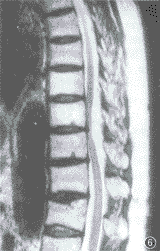

例2 女, 66岁。双下肢麻木、僵硬伴运动受限1年,加重3个月伴小便失禁。体检:脐上三横指平面以下痛、触觉减弱,双腹壁反射、踝反射减弱,病理反射未引出。双下肢肌力 IV级。脑脊液压力和常规检查正常。胸椎 X线片正常。 MRI扫描:T8~9椎管内脊髓后方硬膜外见一4.1 cm× 1.1 cm大小的长梭形病灶,基底靠后。T1WI和T2WI均呈高信号,T1WI信号不均(图5,6)。脂肪抑制技术不能压制病灶高信号。注射Gd-DTPA后, 病灶呈轻度不均匀强化。脊髓受压变细前移。MRI诊断:海绵状血管瘤并出血。手术所见:T8~9水平椎管内硬膜外见一长梭形肿瘤,暗红色,轻度分叶,与硬膜有粘连。未见明显粗大的供血和引流血管。显微镜检查:肿瘤组织由壁薄而大小不等的窦状血管间隙组成,壁为单层内皮细胞,可见含铁血黄素颗粒。病理诊断:海绵状血管瘤并出血。

图5,6 例2。图5为T1WI、图6为T2WI。示T8~9 椎管内脊髓后方硬膜外长梭形病灶, 呈短T1、长T2信号,T1WI信号不均匀,脊髓明显受压变形、前移